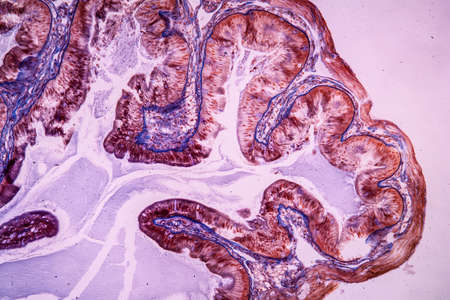

Histopathology of intestinal adenoma, light micrograph, photo under microscope